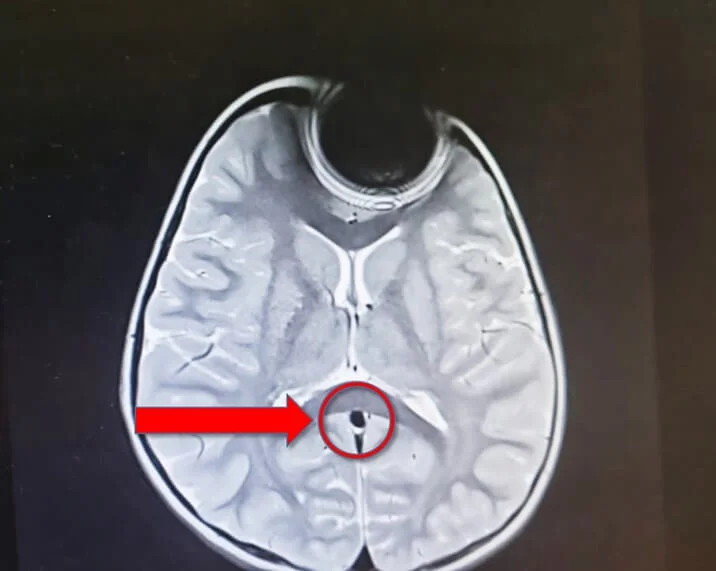

בבדיקות הדימות שבוצעו, נמצאו אינדיקציות להימצאות של גורם זר באפה של הפעוטה סוללה קטנה מה שהוביל לתגובות שונות של המערכת הגופנית של הילדה הקטנה אשר גרמו לאותם סימפטומים.

משנמצא מקור הבעיה, הוצאה הסוללה מאפה של המטופלת על ידי צוות אא"ג, כשהיא תחת טשטוש. לאחר מכן היא נותרה להשגחה ולבסוף שוחררה לביתה כשהיא חשה בטוב.